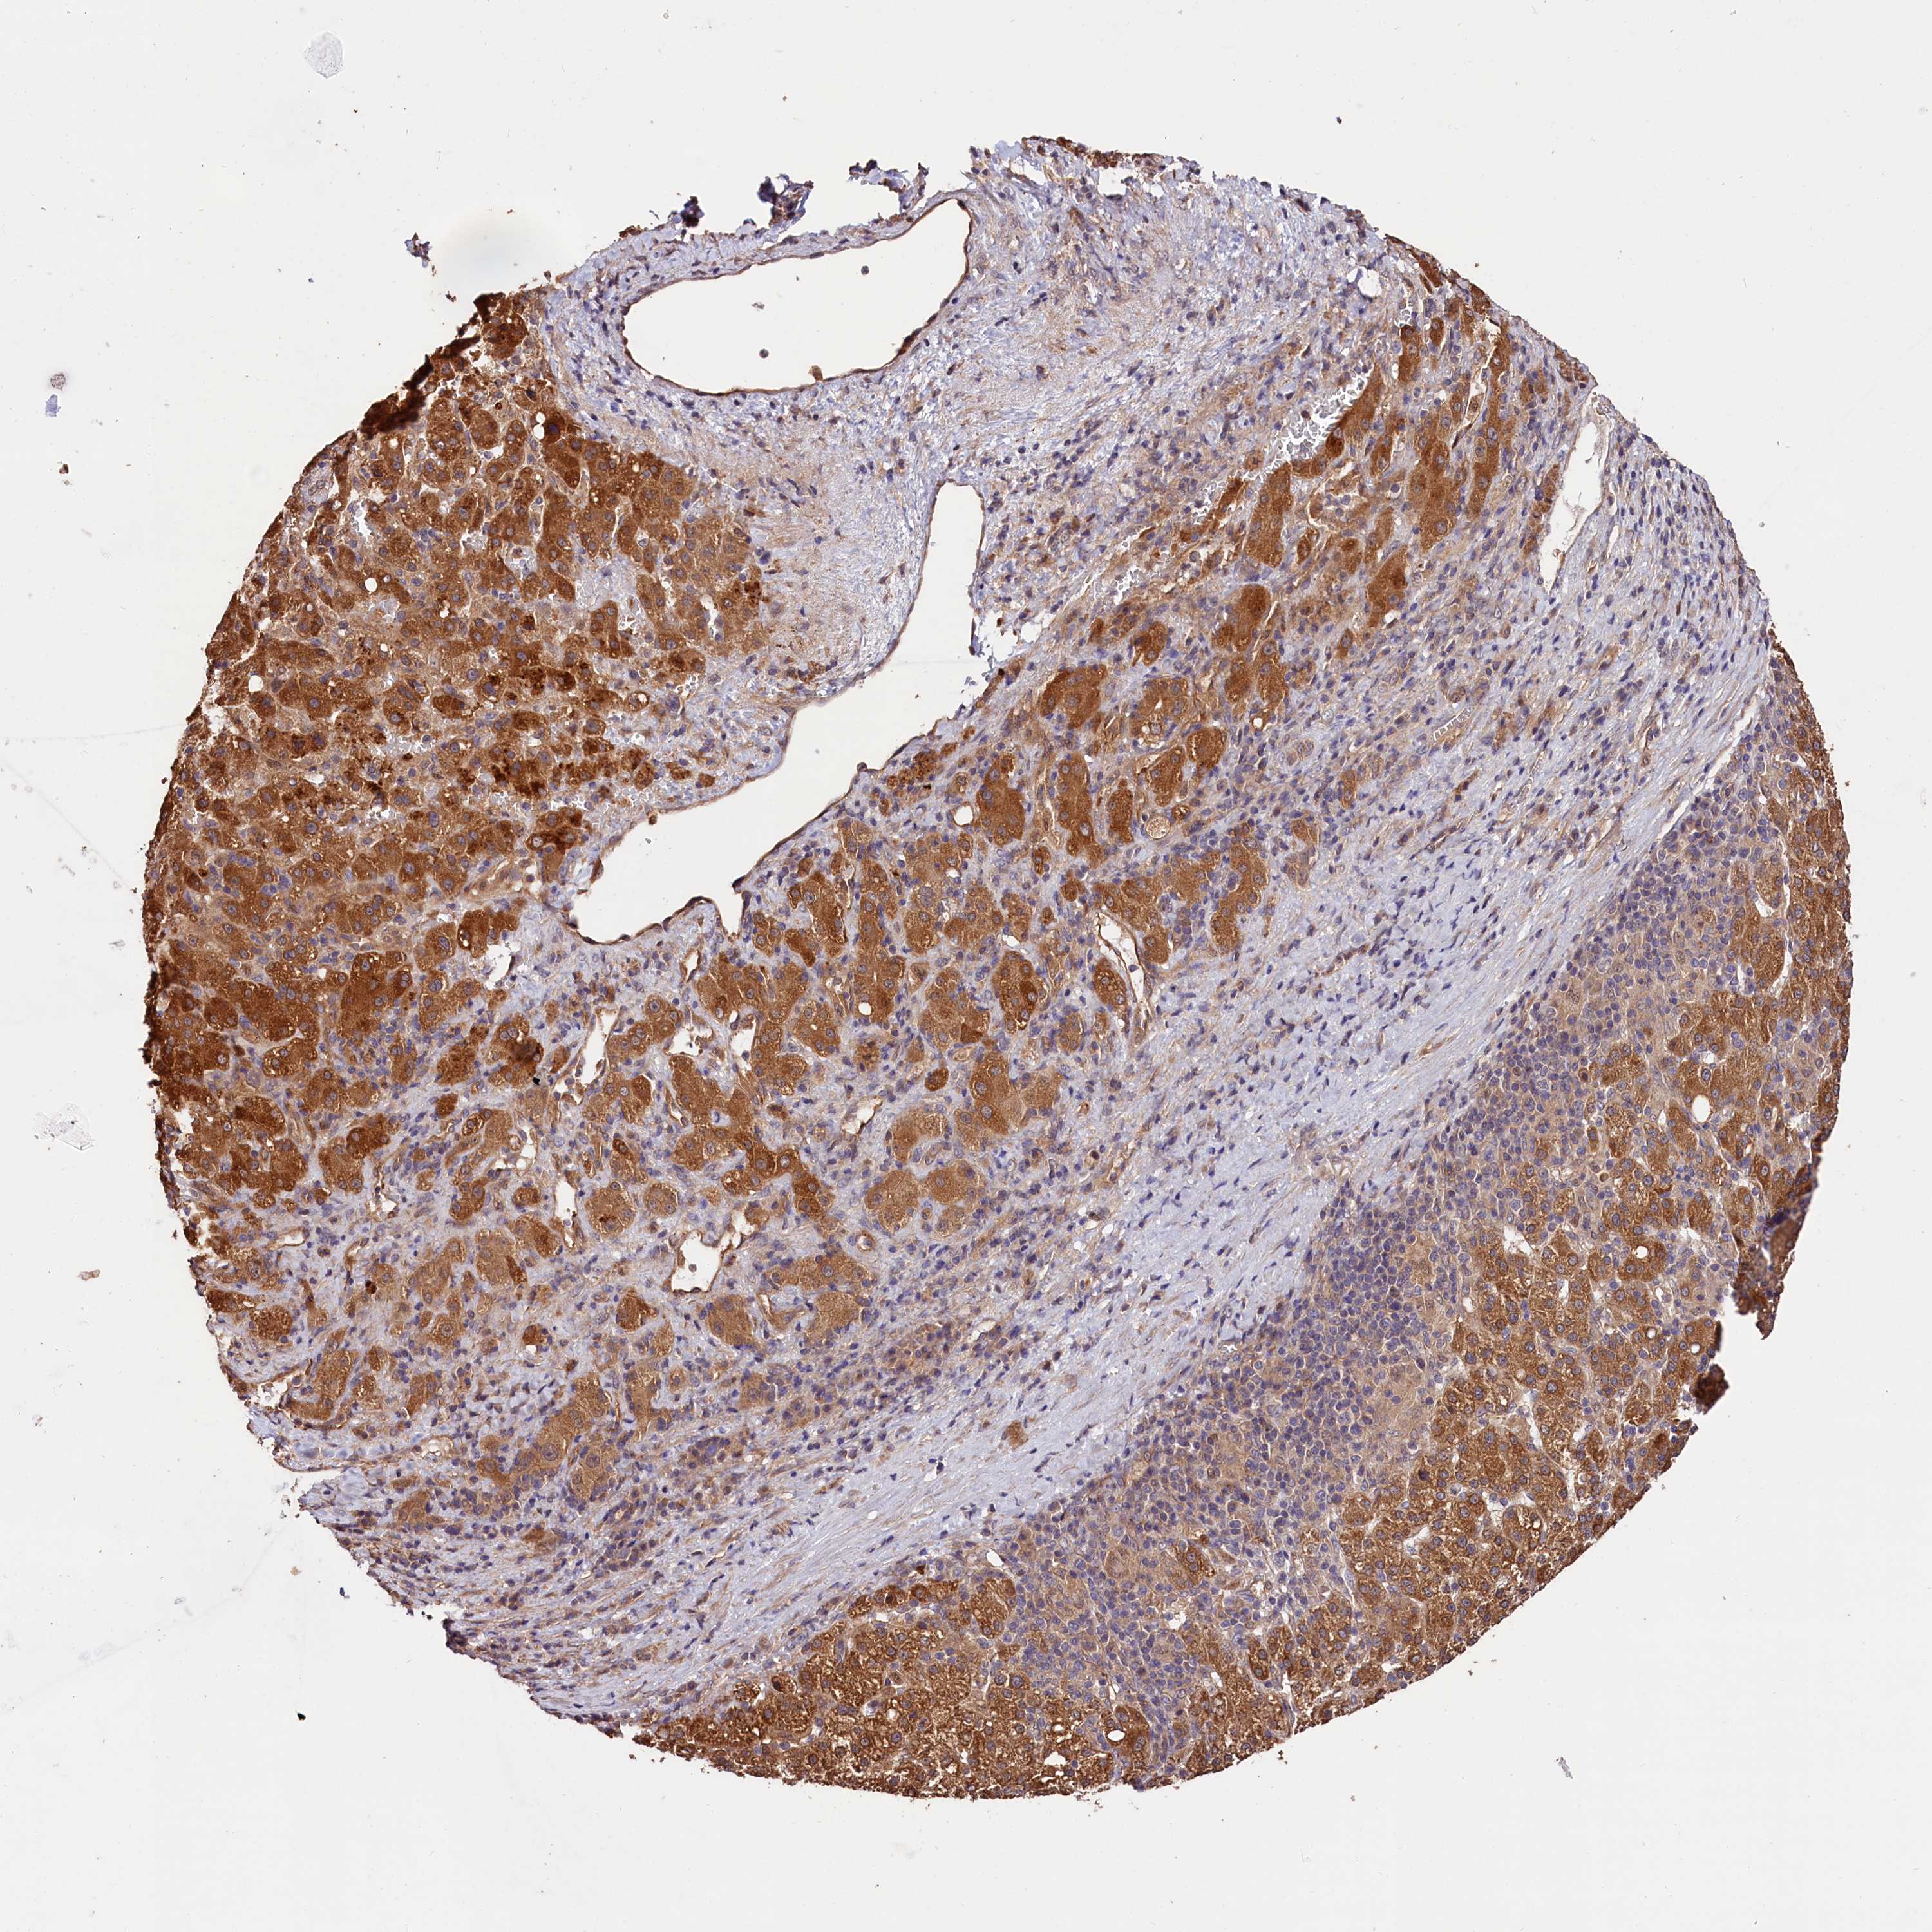

LIVER CANCER - Protein expressioni

A mouse-over function shows sample information and annotation data. Click on an image to view it in a full screen mode. Samples can be filtered based on level of antibody staining by selecting one or several of the following categories: high, medium, low and not detected. The assay and annotation is described here.

Note that samples used for immunohistochemistry by the Human Protein Atlas do not correspond to samples in the TCGA dataset.

Antibody stainingi

Antibody staining in the annotated cell types in the current human tissue is reported as not detected, low, medium, or high, based on conventional immunohistochemistry profiling in selected tissues. This score is based on the combination of the staining intensity and fraction of stained cells.

Each image is clickable and will lead to virtual microscopy that enables deeper exploration of all samples and also displays staining intensity scores, fraction scores and subcellular localization as well as patient and tissue information for each sample.

Antibody HPA041008

Antibody HPA041307

Staining

High

Medium

Low

Not detected

Intensity

Strong

Moderate

Weak

Negative

Quantity

>75%

75%-25%

<25%

None

Location

Nuclear

Cytoplasmic/membranous

Cytoplasmic/membranous,nuclear

Cholangiocarcinoma

Carcinoma, Hepatocellular, NOS